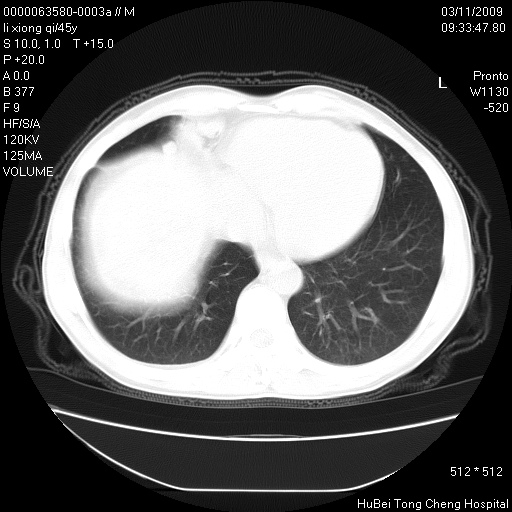

患者 男,45岁。胸痛,咳嗽伴痰中带血1月余。

临床诊断:肺结核?

胸部ct轴位平扫(层厚10mm,螺距1.5,重建间隔10mm),图像如下: